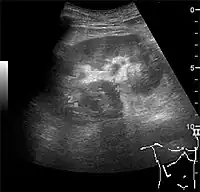

Figure 8. Cortical solid mass, which later was shown to be renal cell carcinoma. Measurement of the solid mass on the US image is illustrated by '+' and a dashed line.[1]

Figure 9. Renal cell carcinoma with both cystic and solid components located in the cortex. Measurement of tumor on the US image is illustrated by '+' and a dashed line.[1]

A solid renal mass appears in the US exam with internal echoes, without the well-defined, smooth walls seen in cysts, often with Doppler signal, and is frequently malignant or has a high malignant potential. The most common malignant renal parenchymal tumor is renal cell carcinoma (RCC), which accounts for 86% of the malignancies in the kidney. RCCs are typically isoechoic and peripherally located in the parenchyma, but can be both hypo- and hyper-echoic and are found centrally in medulla or sinus. The lesions can be multifocal and have cystic elements due to necrosis, calcifications and be multifocal (Figure 8 and Figure 9). RCC is associated with von Hippel–Lindau disease, and with tuberous sclerosis, and US has been recommended as a tool for assessment and follow-up of renal masses in these patients.[1]

However, US is not the primary modality for the evaluation of solid tumors in the kidney, and CT is the first choice modality. Nevertheless, hemorrhagic cysts can resemble RCC on CT, but they are easily distinguished with Doppler ultrasonography. In RCCs, Doppler US often shows vessels with high velocities caused by neovascularization and arteriovenous shunting. Some RCCs are hypovascular and not distinguishable with Doppler US. Therefore, renal tumors without a Doppler signal, which are not obvious simple cysts on US and CT, should be further investigated with CEUS, as CEUS is more sensitive than both Doppler US and CT for the detection of hypovascular tumors.[1]